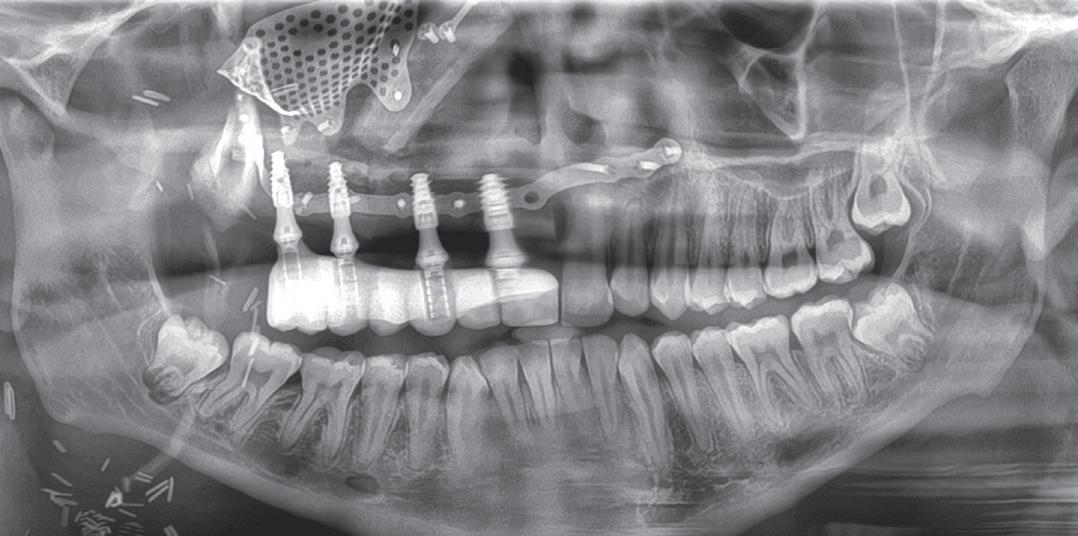

The surgery is called Jaw in a Day, and James was the first patient in Tennessee and the Mid-South to undergo it. Performed by a multidisciplinary team of surgeons from the UT Health Science Center, the procedure involved removing the tumor, building the facial bones, eye socket, and jaw out of James’s leg bone, and installing dental implants and prosthetic teeth—all within one day.

“This helps surgeons appropriately stage surgeries in which multiple services are involved and, furthermore, allows surgeons to plan for combined cases in which surgeons will provide care under one operating room visit when appropriate,” says Associate Professor and Program Director Brett Wilson, DDS, who led the oral and maxillofacial surgery team in the Jaw in a Day surgery. “This can prevent patients from unnecessarily assuming the risk of general anesthesia multiple times. All of this just results in patients getting ideal and efficient treatment.”

Using James’s CT scans, the surgeons created 3D computer models of the skull and the leg bone and essentially performed the surgery virtually. “This allows us to plan the ideal placement of each component and use multiple patient-specific materials, including guides to help with tumor removal, orientation and positioning of the fibula, and orientation of the dental implants within the fibula. It also allows us to have custom, 3D-printed titanium hardware that helps ensure everything fits together seamlessly,” Dr. Wilson says.

The team used the computer models to 3D print life-size replicas of James’s skull to use during surgery. They also built custom cutting slots to guarantee precise cuts while recreating the pieces of the jaw and custom prosthetic teeth that matched James’s natural jawline and bite.

to connect the blood vessels and ensure the bone’s survival. Finally, Dr. Wilson and Dr. Brooks attached the prosthetic teeth to the dental implants.

In an operating room at Methodist University Hospital, Burton Wood, MD, assistant professor of head and neck surgical oncology, first removed the tumor. The surgeons then removed the damaged maxilla, or upper jaw, and the orbital floor, the bottom of the eye socket. The reconstructive team meticulously cut James’s fibula to create the shape of the face and jaw.

While the bone was still connected to the leg via blood vessels, the team fixed the fibula onto a 3D-printed skull model, allowing Dr. Wilson and Jeffrey Brooks, DMD, professor and chair of the Department of Oral and Maxillofacial Surgery, to place dental implants into the bone. Dr. Eid and his team then removed the fibula from the model and attached it to James’s face, using a microscope